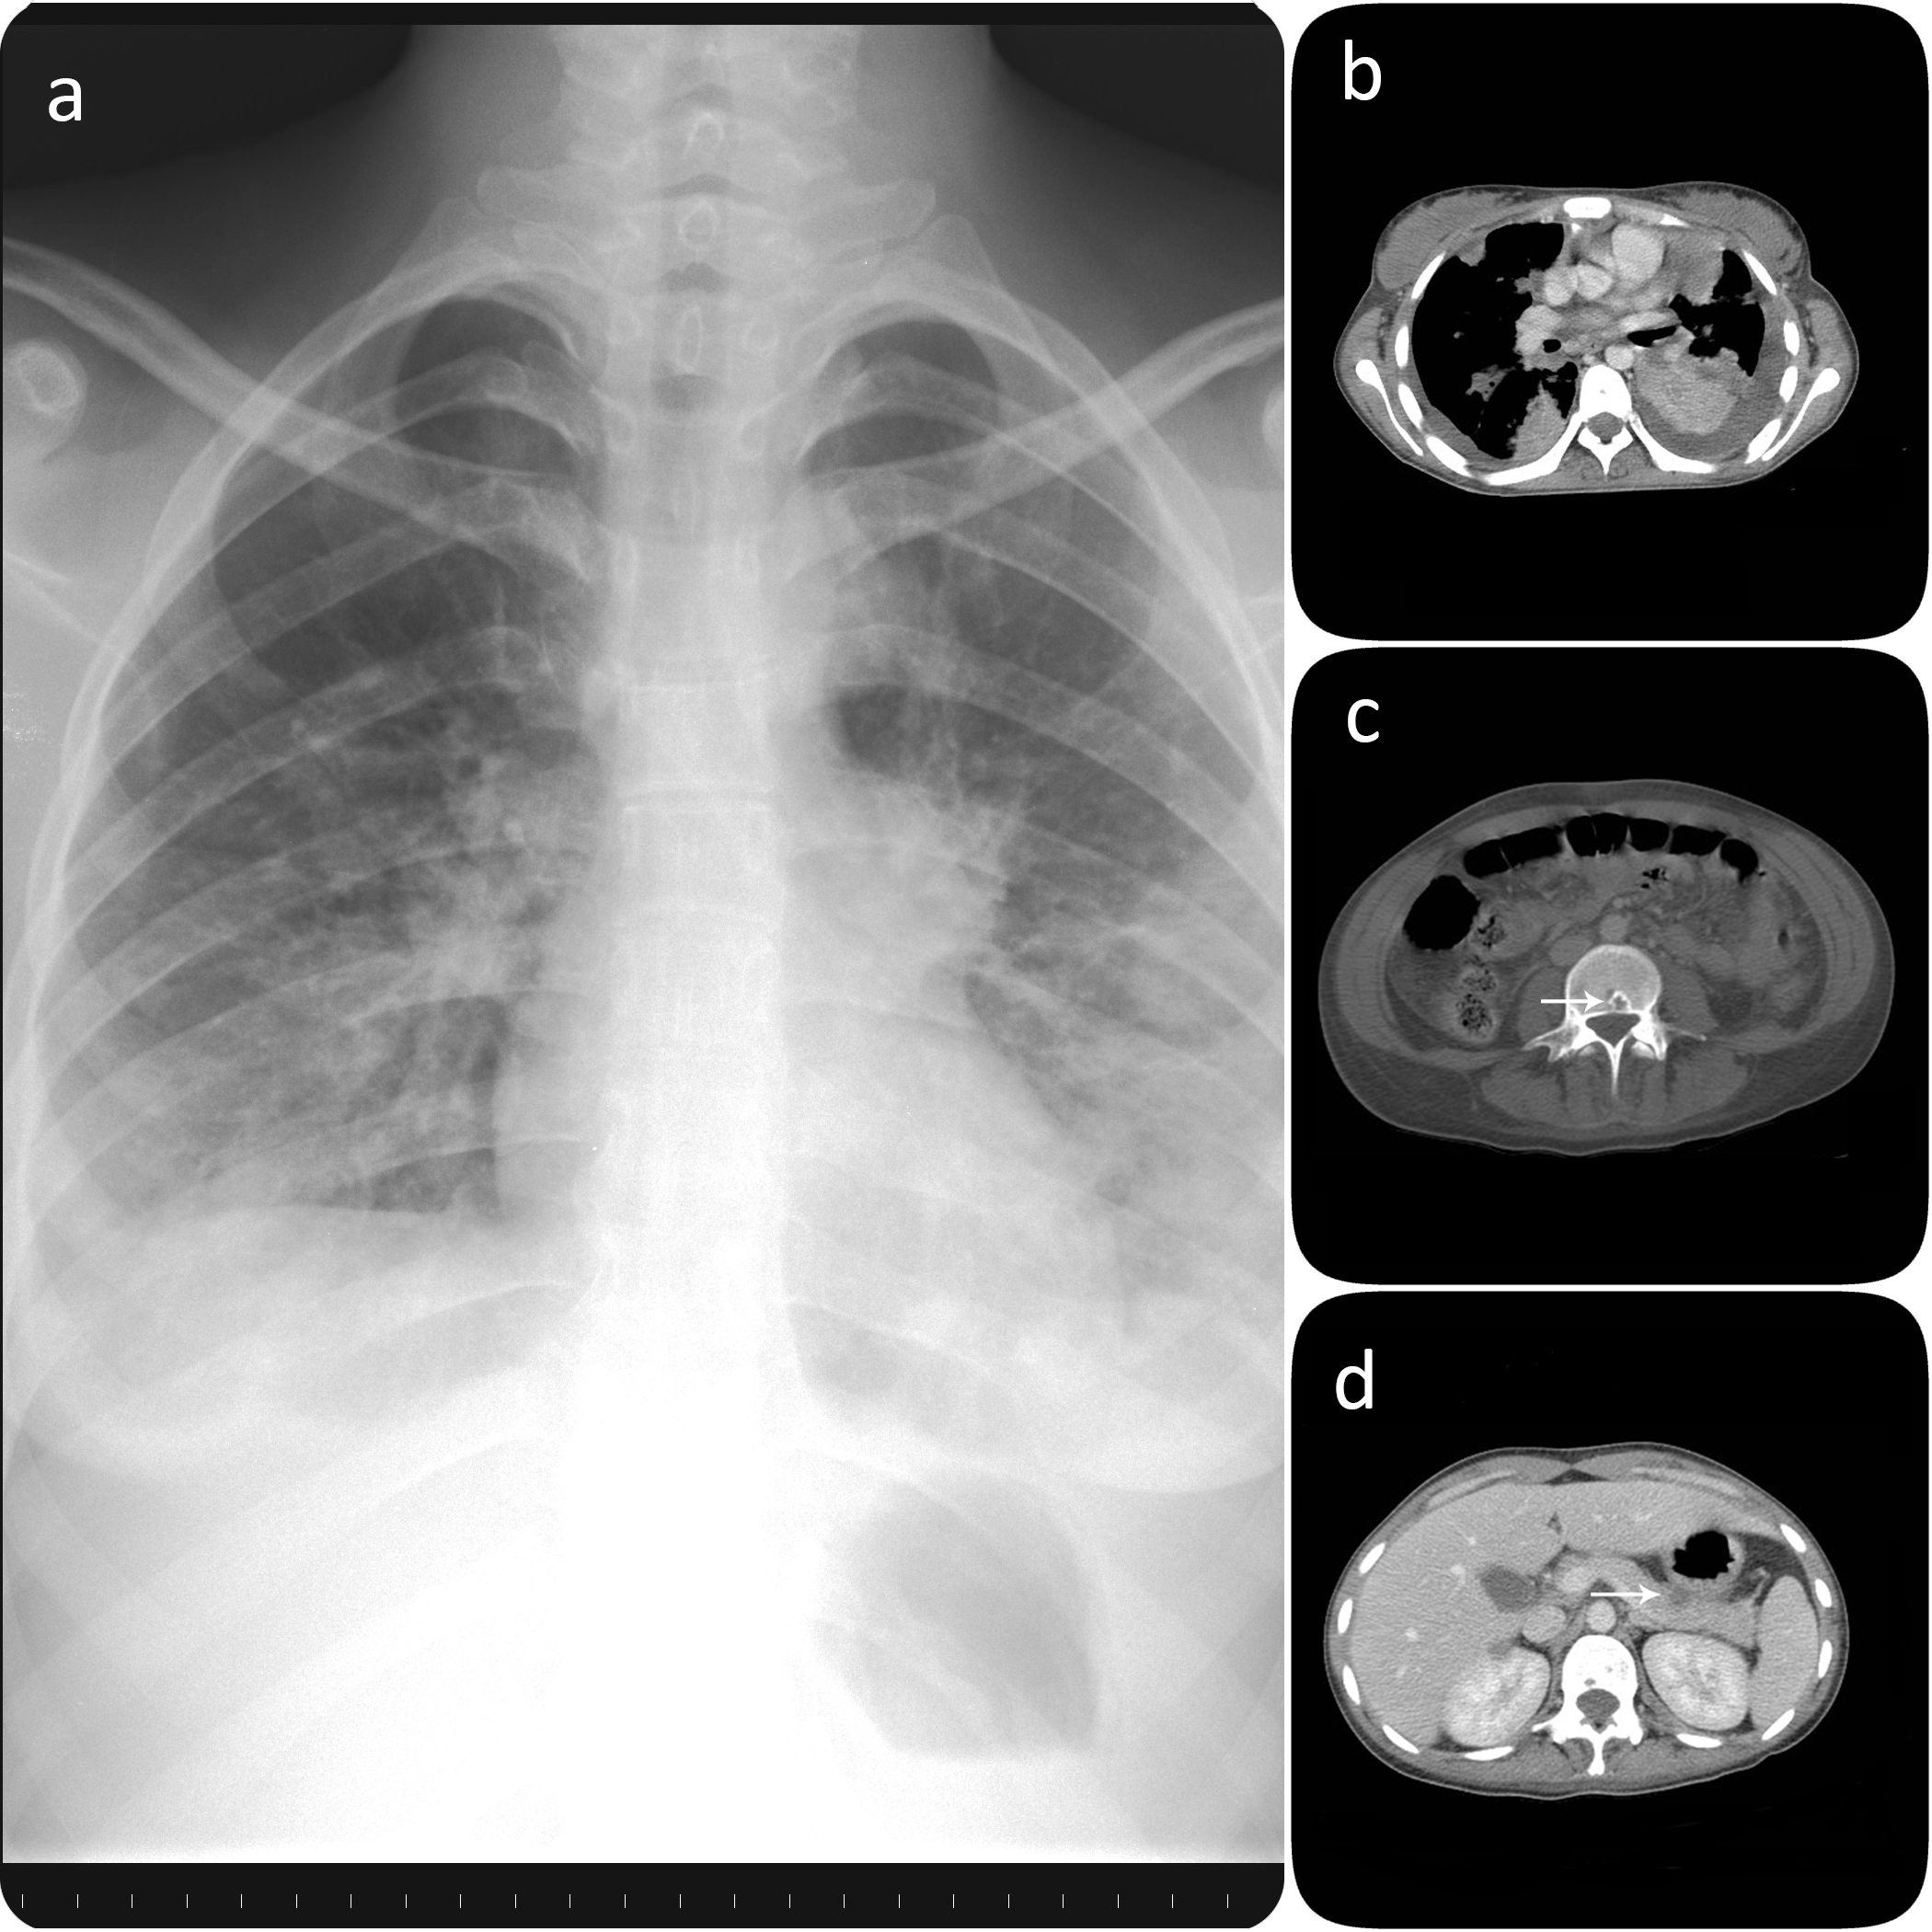

Caso clínico. Presentamos el caso de una paciente de 20 años que consultó por un cuadro de evolución subaguda. Se obtuvo una RMN cerebral que demostró la presencia de una lesión temporal derecha, que sugería un glioma de alto grado como primera posibilidad diagnóstica. Se intervino a la paciente, realizando una resección macroscópicamente completa de la lesión. Se administró tratamiento radioterápico y quimioterápico adyuvante, de acuerdo con el protocolo de nuestro centro. Cinco meses después de la cirugía la paciente consultó por dolor torácio y tos seca. Se realizó un TAC toraco-abdomino-pélvico, que mostró la presencia de infiltrados pulmonares bilaterales con derrame pleural asociado, un nódulo pancreático y varias lesiones vertebrales líticas. Las lesiones pulmonares fueron biopsiadas. El diagnóstico anatomopatológico fue de metástasis de glioblastoma multiforme. La paciente falleció ocho meses después del diagnóstico inicial